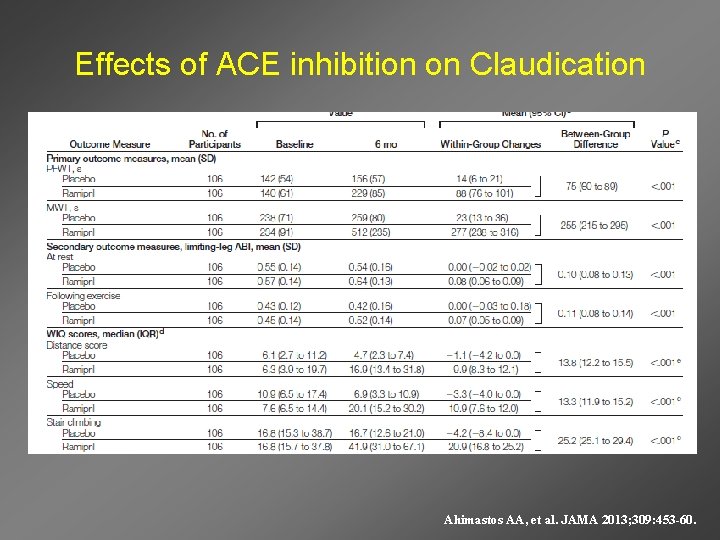

Effects of ACE inhibition on Claudication Ahimastos AA, et al. JAMA 2013; 309: 453 -60.

Additional Effects of ACE Inhibition in PAD Ahimastos AA, et al. JAMA 2013; 309: 453 -60.